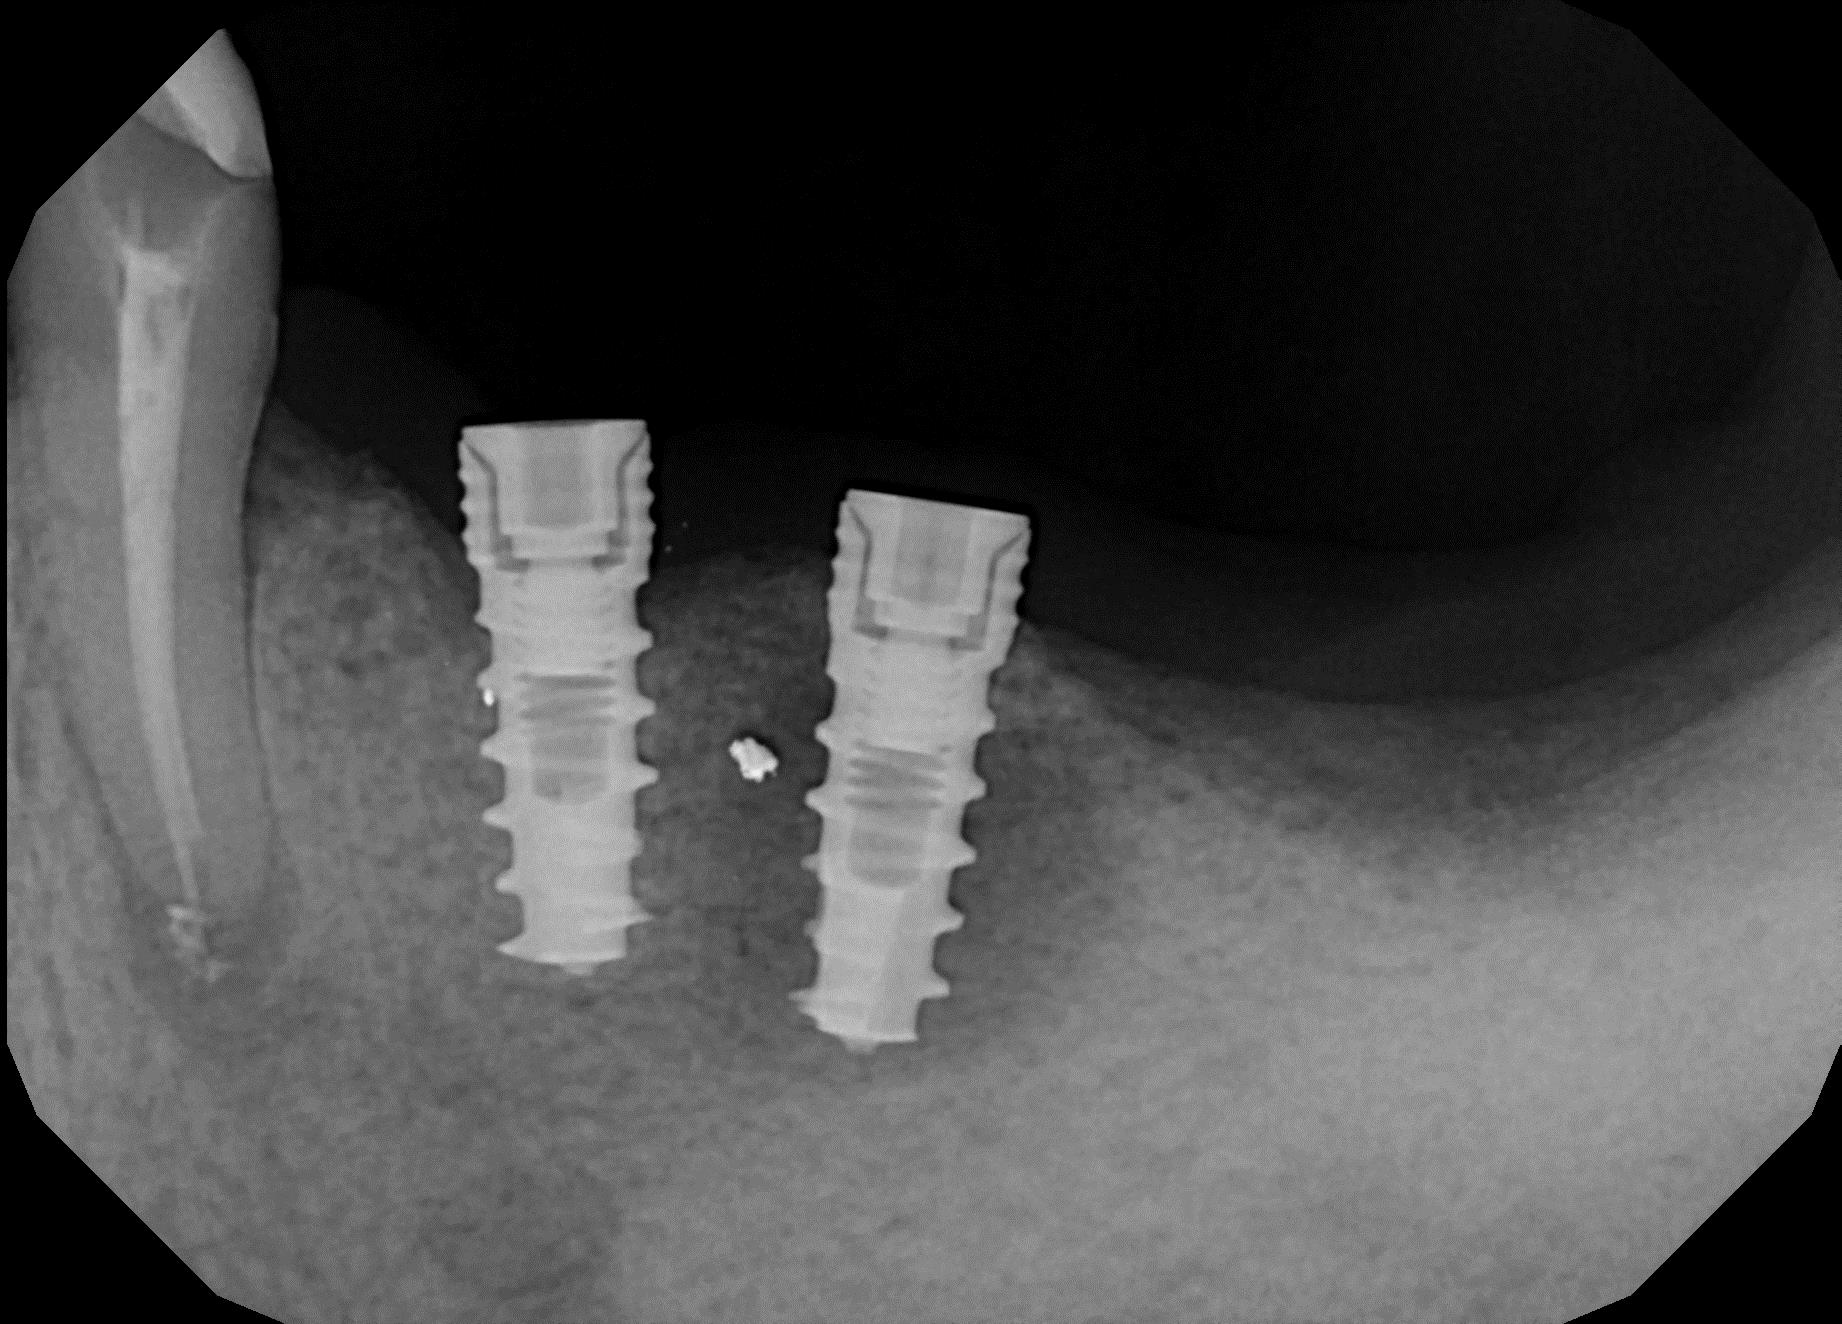

Исследование на рентгене после имплантации зубов

Раздел: Снимки-откровения